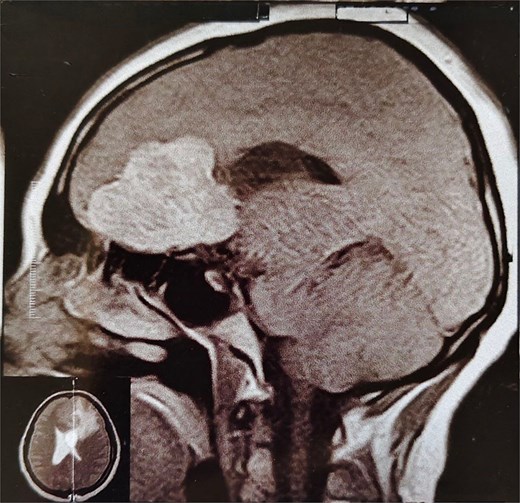

A 44-year-old right-handed woman presented with a two-month history of headache and blurred vision. Her medical history included hypertension and type 1 diabetes mellitus. She reported gradually worsening intermittent headache and bilateral visual blurring, more pronounced in the right eye. Symptoms exacerbated with physical exertion and were unrelieved by analgesics, leading to her referral. Examination revealed a conscious, alert patient with right eye proptosis. Visual acuity was 6/6 (left eye) and 6/9 (right eye). Fundoscopy identified bilateral Grade 3 papilledema. Non-contrast brain CT demonstrated a well-defined, isodense, dural-based extra-axial lesion in the left frontal region with a cystic component, measuring approximately 5.5 × 4.3 × 4.2 cm. It was associated with mild perilesional edema, mass effect, and a subtle contralateral falx shift. The initial impression was an atypical meningioma (Fig. 1). Subsequent MRI confirmed a large, falcine-based lesion that appeared isointense on T1- (Fig. 2) and T2-weighted images, demonstrating intense homogeneous enhancement post-contrast (Fig. 3). Signal voids suggested calcifications. The patient underwent gross total excision via a bilateral frontal craniotomy. The tumor was intradural and extra-axial, elevating the frontal lobe and was easily accessible; therefore, neither neuronavigation nor other intra-operative localization aids were utilized. Intraoperatively, the olfactory tract could not be clearly identified. A gap in the anterior cranial base was noted, but as there was no evidence of dural invasion or cerebrospinal fluid leak, no sealant was required. Gross examination of the resected specimen revealed a well-circumscribed, white nodule. Microscopically, sections showed benign spindle cell proliferation with alternating Antoni A and Antoni B areas (Fig. 4). Antoni A regions displayed nuclear palisading and Verocay bodies (Fig. 5), while Antoni B areas were edematous and myxoid (Fig. 6). No mitotic figures or atypia were seen. The definitive diagnosis was a benign olfactory groove schwannoma, notable given the initial radiological suspicion of meningioma. Her postoperative course was uneventful. A postoperative non-contrast CT brain obtained 48 hours after surgery confirmed gross total resection (Fig. 7). She was discharged with scheduled follow-up to monitor recovery and visual symptoms.

MRI brain with IV contrast (sagittal midline view) showing a homogeneously enhancing mass based on the cribriform plate of the ethmoid, displacing the frontal lobe upward and posteriorly.